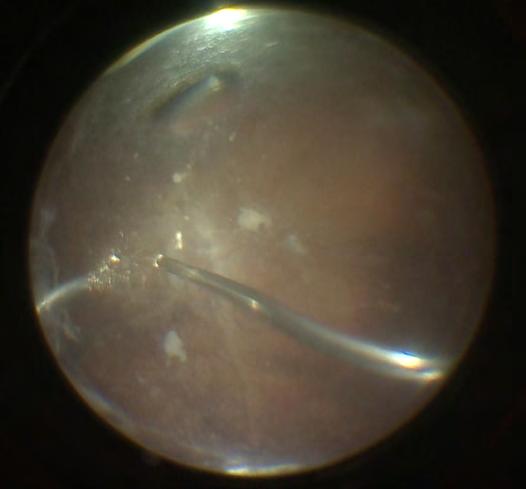

Infine, viene delineata proprio la Small Incision. Questa incisione serve da punto di ingresso per il chirurgo che provvederà a slamellare e rimuovere il lenticolo (Fig. 3 a-b-c).

Slamellamento ed estrazione del lenticolo

Alla fine del trattamento laser, che in genere dura circa 28-29 secondi (VisuMax 500 kHz), il chirurgo procederà con lo slamellamento e quindi la rimozione del lenticolo attraverso l'incisione di accesso. Questo processo richiede abilità e precisione, motivo per cui la learning curve di questa metodica appare essere piuttosto alta rispetto alle precedenti tecniche descritte. I passaggi corretti prevedono lo scollamento prima della faccia anteriore del lenticolo (quella più superficiale) e successivamente di quella posteriore (più profonda) su tutti i 360° al fine di non lasciare ponti residui o eventuali frammenti del lenticolo nella tasca.